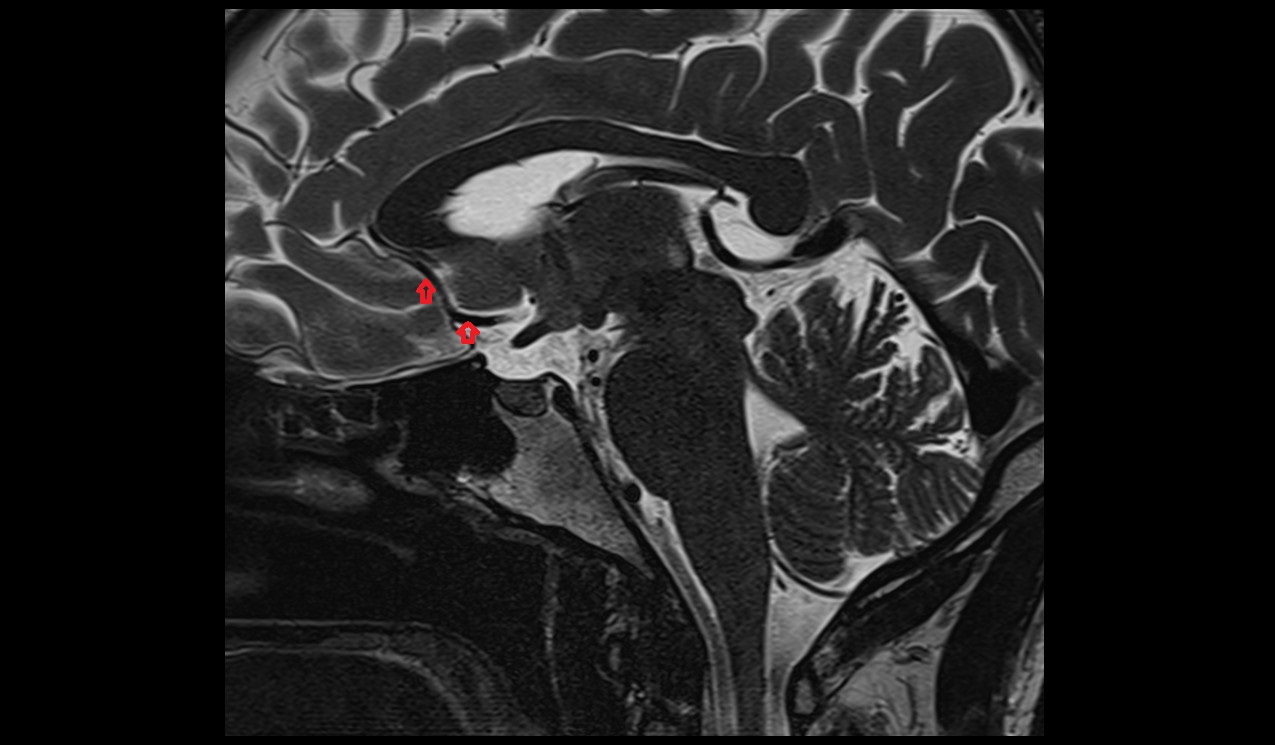

- Pituitary stalk

- Pituitary gland

- Anterior lobe of pituitary gland

- Posterior lobe pituitary gland